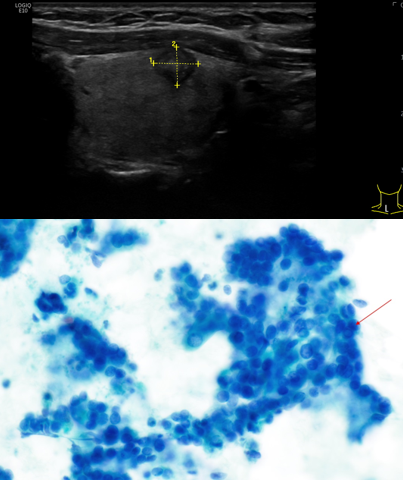

In unserem hausinternen Punktionsambulatorium werden folgende Organe/Läsionen Ultraschall-gesteuert punktiert:

• Schilddrüse

• Lymphknoten

• Speicheldrüsen

• Mamma

• Weichteiltumoren

• Haut-/Schleimhautläsionen